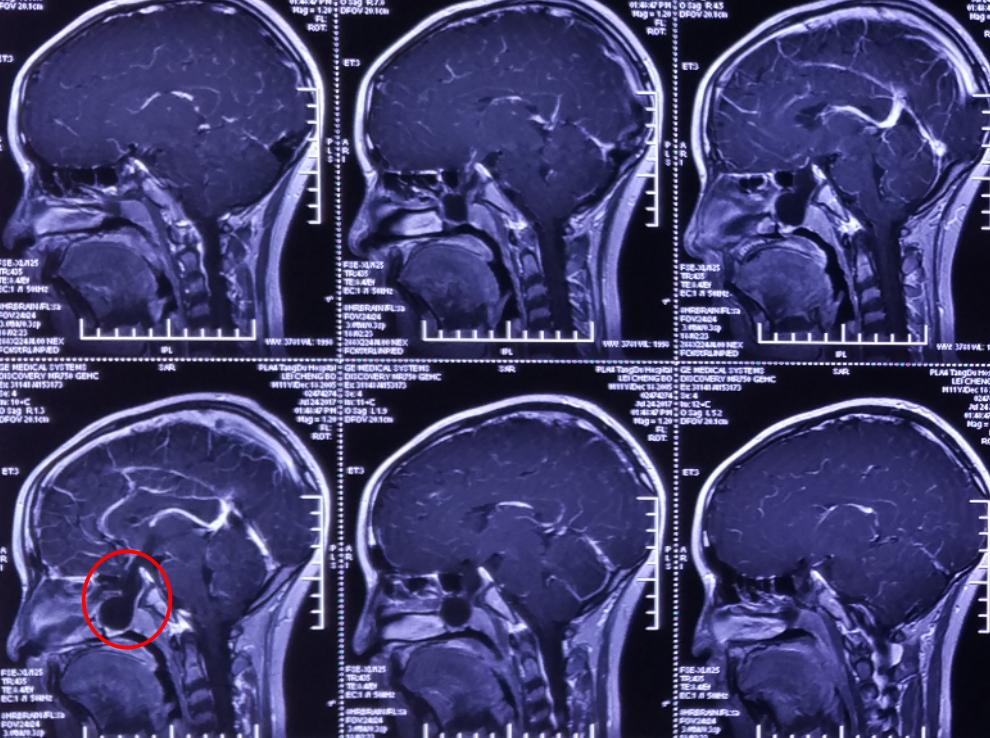

术后影像